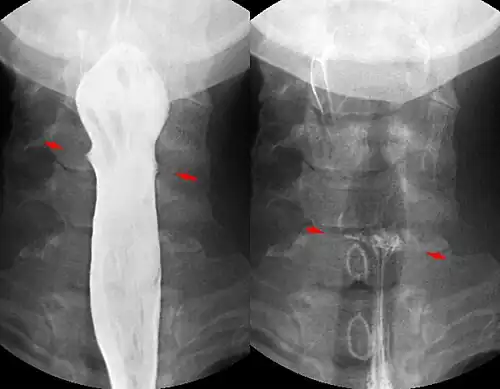

If the person who swallowed the foreign body is doing well, usually an x-ray image will be taken which will show any metal objects, and this will be repeated a few days later to confirm that the object has passed all the way through the digestive system. Also it needs to be confirmed that the object is not stuck in the airways, in the bronchial tree.

Abdominal X-ray showing small packages of cocaine swallowed by a trafficker.

Abdominal X-ray showing small packages of cocaine swallowed by a trafficker. -

Fishbone pierced in the upper esophagus.Left image during swallowing contrast medium, right image after swallow only dimly visible.

Fishbone pierced in the upper esophagus.Left image during swallowing contrast medium, right image after swallow only dimly visible.